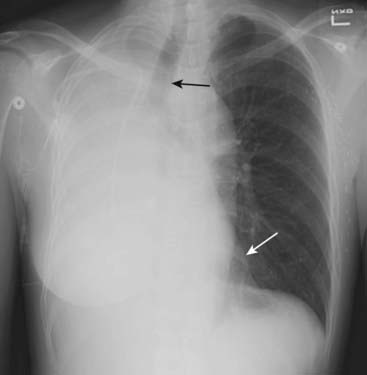

Figure 5-3 Atelectasis of the left lung.

There is complete opacification of the left hemithorax with shift of the trachea (solid black arrow) and the esophagus (marked here by a nasogastric tube, dotted black arrow) toward the side of the atelectasis. The right heart border, which should project about a centimeter to the right of the spine, has been pulled to the left side and is no longer visible. The patient had an obstructing bronchogenic carcinoma in the left main bronchus.

image Atelectasis of the entire lung (see Figs. 5-3 and 5-4)

On the frontal radiograph:

There is opacification of the atelectatic lung due to loss of air.

The hemidiaphragm on the side of the atelectasis will be silhouetted by the nonaerated lung above it.

There is a shift of all of the mobile structures of the thorax is toward the side of the atelectatic lung.

On the lateral radiograph:

The hemidiaphragm on the side of the atelectasis will be silhouetted by the nonaerated lung above it. Look closely and you’ll see only one hemidiaphragm on the lateral exposure, instead of two.